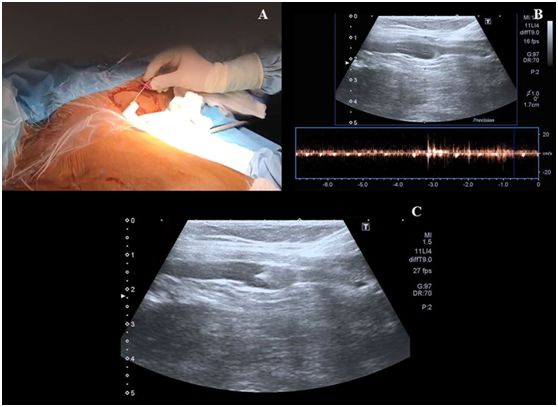

第三步,操作者左手持超声探头,右手持带穿刺针的注射器在超声引导下对腋静脉进行穿刺,超声长轴图像平面内同时可见静脉腔及穿刺针(图2)。皮肤穿刺点尽可能靠近超声探头远端的短边上。当穿刺针触碰到静脉前壁时,在压力的作用下,静脉壁会出现下沉塌陷,因此,此时应快速进针。

当在腋静脉腔内观察到针尖的斜面时(一个白点),可以很容易地确定穿刺针在血管内的位置(图2C)。也可以通过回抽血液1-2ml来确认穿刺针的位置是在静脉内。当患者血压较低时,无搏动性血流出现并不能排除穿刺到动脉的可能。随后置J形导丝,导丝的位置也可能在超声实时下确认(图3,A-C)。也可以通过颈部超声探查来排除导丝进行左侧颈内静脉。导丝置入长度应限定在20cm,以避免引起心律失常。随后扩张皮肤穿刺点,用Seldinger技术置入导管。在输注任何液体之前,回抽确认导管远端是否在血管腔内,随后再用肝素盐水冲洗导管。导管置入深度为20cm。

图2,A 沿超声探头长轴插入穿刺针;B 超声视窗下可见穿刺针进行静脉;C 超声视窗下看到的血管内穿刺针斜面。